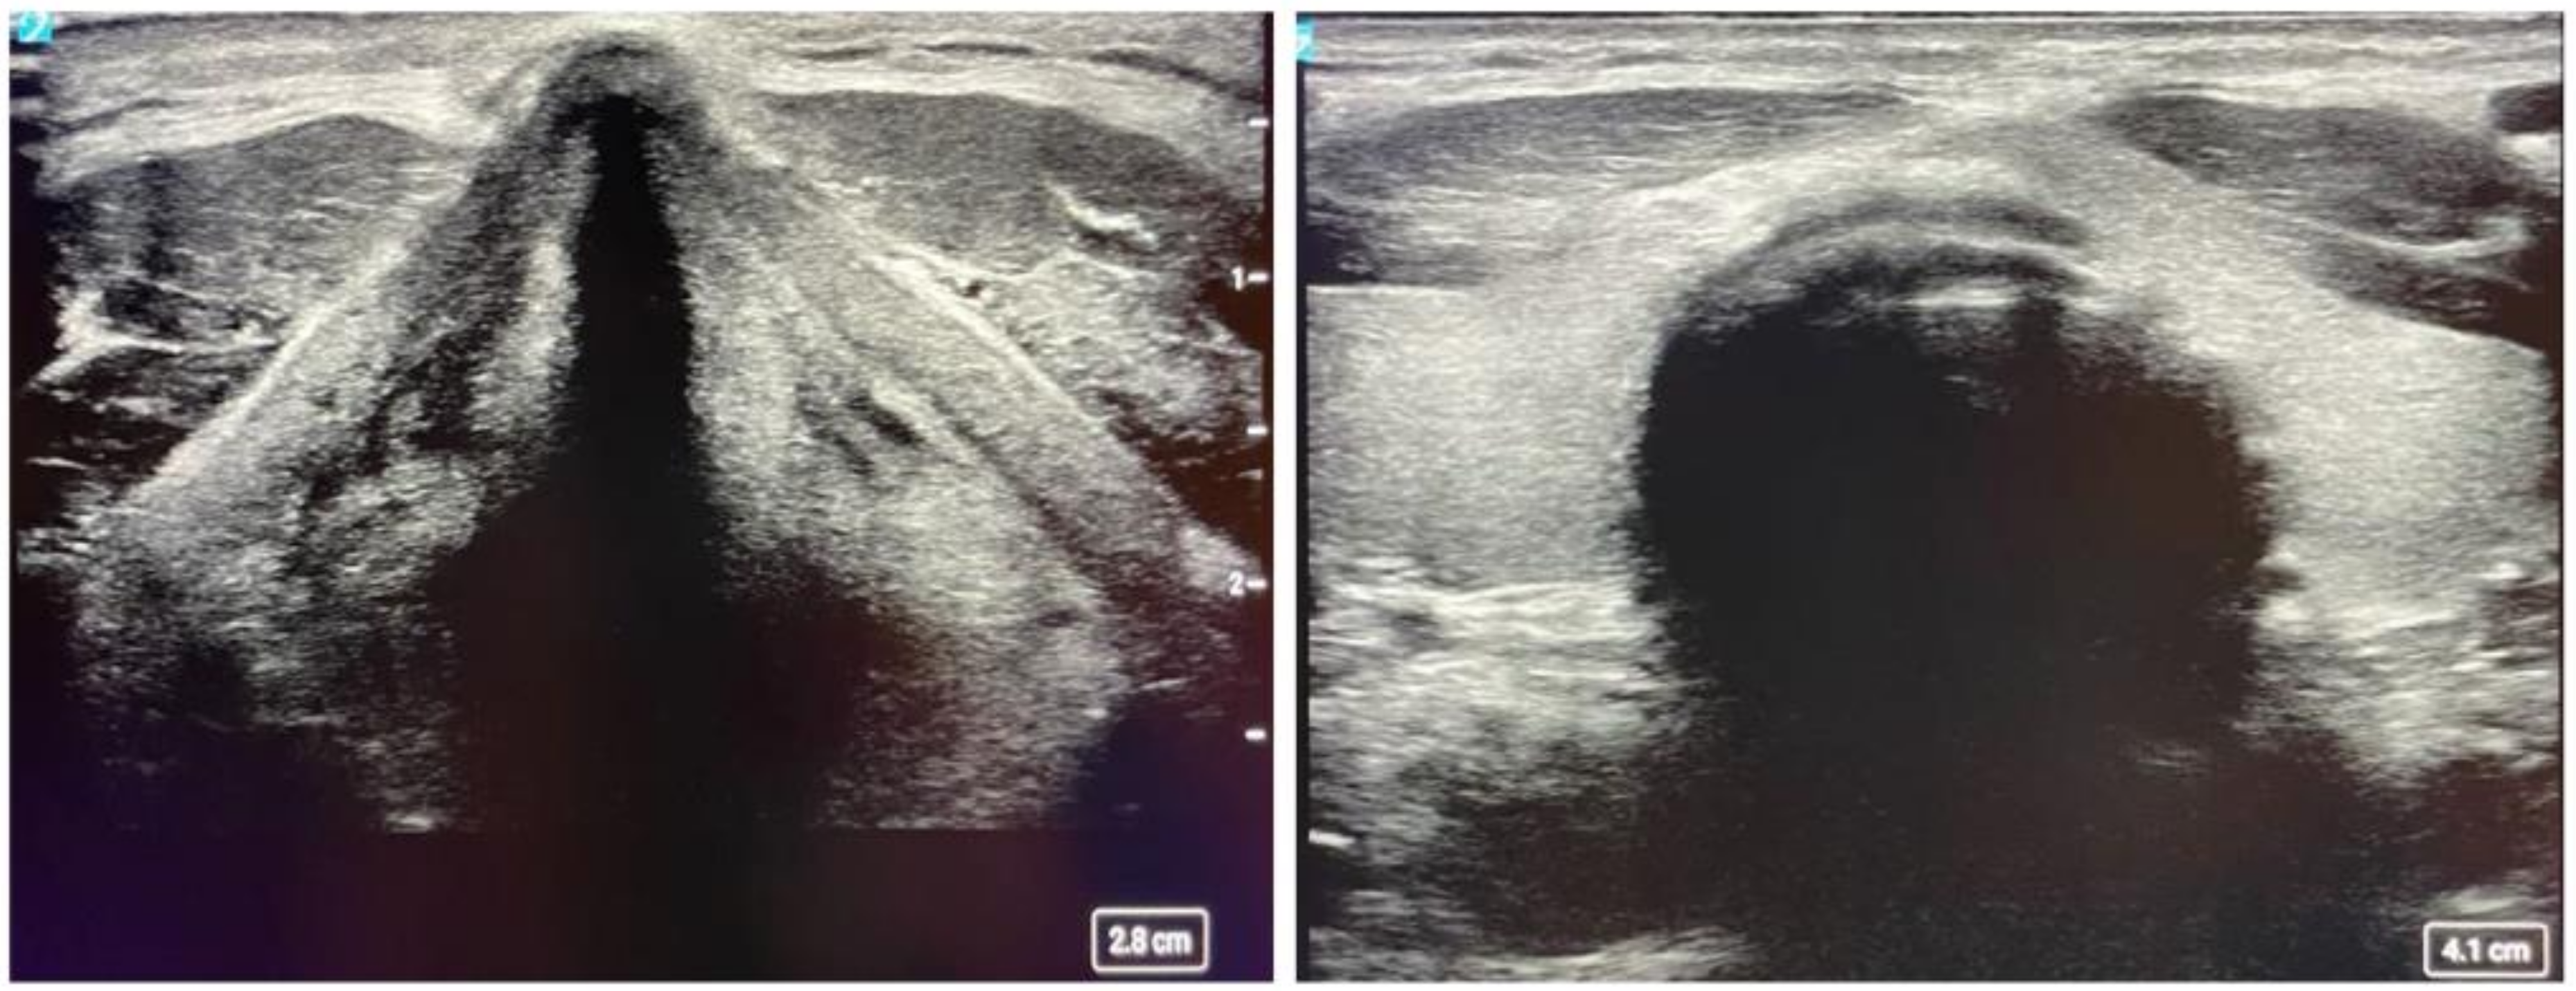

2.5. Peripheral Ultrasound